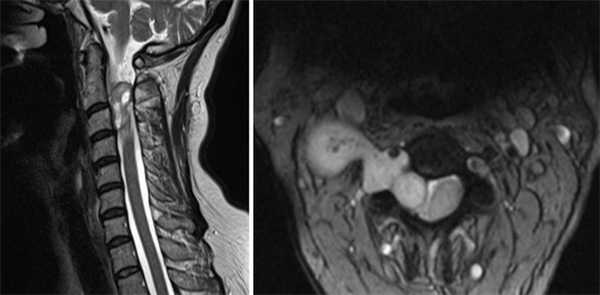

МРТ шейного отдела позвоночника в сагиттальной и аксиальной плоскостях. На уровне С2-С3 позвонков отмечается экстрамедуллярное образование, распространяющееся в правое межпозвонковое отверстие, неправильной формы, неоднородной кистозно-солидной структуры. МР-сигнал от спинного мозга не изменен, спинной мозг компремирован и смещен влево.